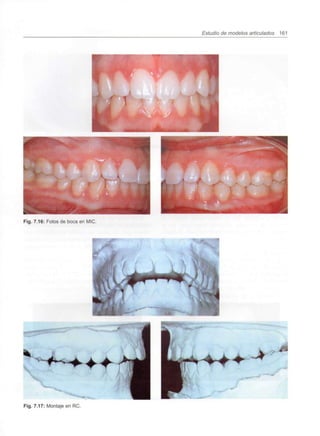

Capítulo 7 - Estudio de modelos articulados 151

Análisis de un caso clínico 160